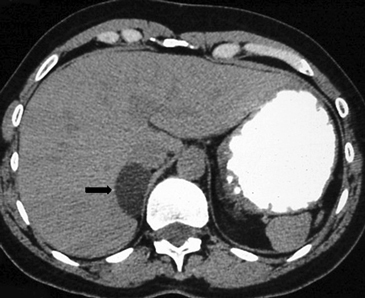

En TC sin contraste por lo general se observa una masa heterogénea, especialmente en caso de lesiones de mayor tamaño por la presencia de necrosis. Entre un 19 a 33% de los casos se identifican calcificaciones. Luego de la administración de contraste su refuerzo es heterogéneo y su patrón de lavado es consistente con una enfermedad maligna (Figura 22).